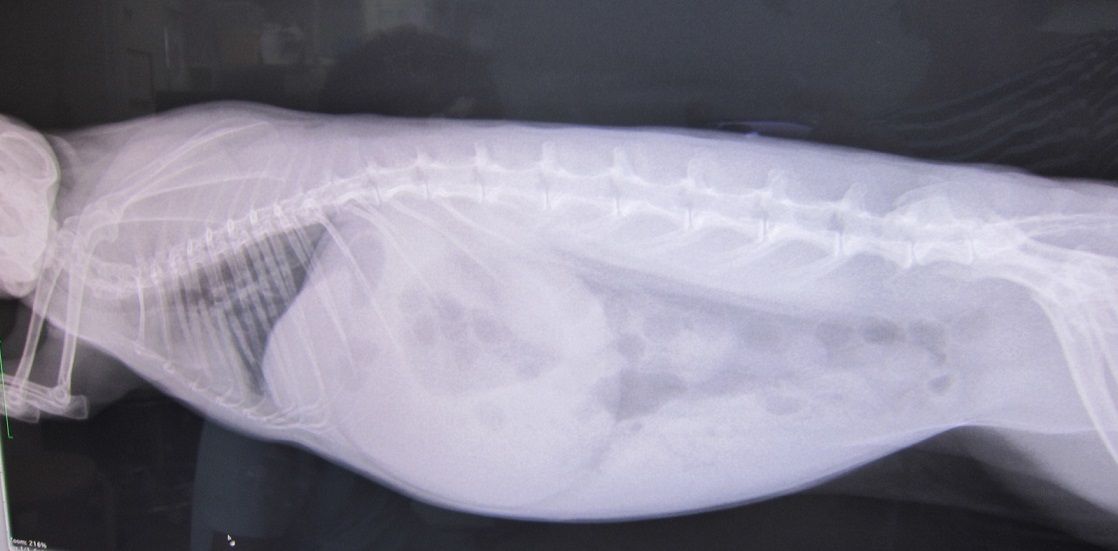

(赤丸は異変発見すぐに撤収した排泄物)

1つだけやけど出た

その後、牧草もぐもぐから始まっての…

出だした出だした

排泄物もお見事でした